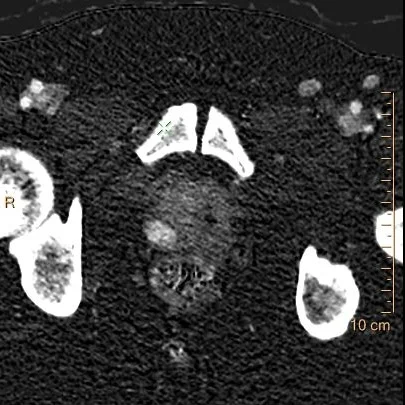

Now turn on spectral CT. Attenuation on virtual non-contrast is almost the same on both sides, so there is no calcification or hemorrhage. On the iodine map, the right posterior nodule has about 3.25 mg/mL of iodine, versus 0.94 mg/mL on the left side. This is a ratio of more than 3.

The nodule stands out like a lightbulb. This illustrates a great inherent strength of spectral imaging, where we can manipulate images to greatly increase contrast to noise ratio. Spectral curves add another level of information, and in this case, they are clearly very different.

Iodine map: The right PZ nodule is a lightbulb!

Iodine map: So much more of a difference!